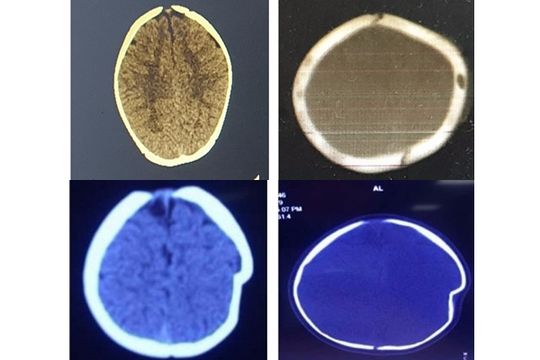

Người đàn ông ở Phú Thọ bất ngờ hôn mê sau 2 tháng ngã xe: Lời cảnh tỉnh với chấn thương 'tưởng là nhẹ'

Sau 2 tháng ngã xe đạp điện, người bệnh bất ngờ xuất hiện rối loạn ý thức, đau đầu dữ dội và hôn mê, phải đến bệnh viện cấp cứu.

Bị ngã xe máy, một tháng sau người đàn ông được phát hiện máu tụ trong não

Anh N.X.C (40 tuổi, Hà Nội) vừa được phẫu thuật thành công tại Bệnh viện Bệnh Nhiệt đới Trung ương. Anh bị máu tụ trong não sau một tai nạn xe máy, có nguy cơ liệt nửa người bên phải.